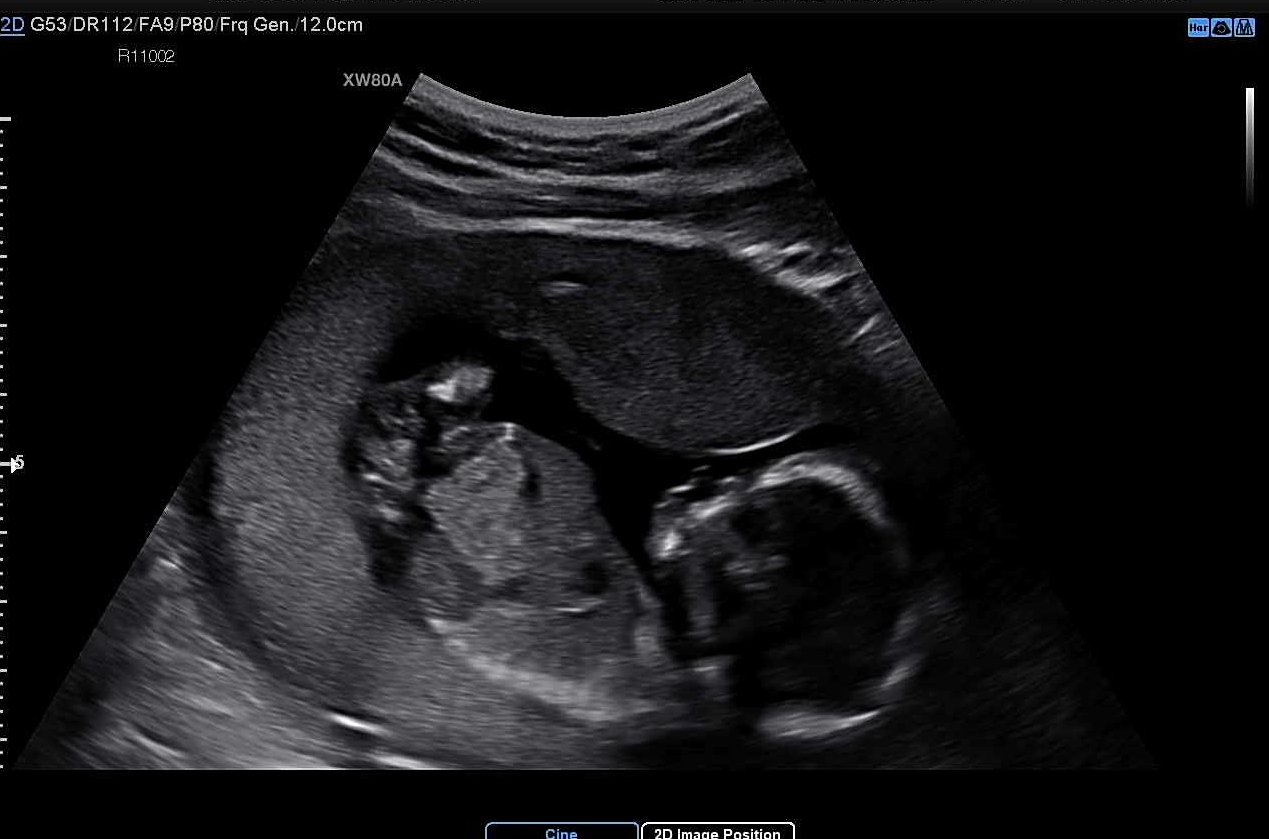

아, 그리고 그때 너가 남자아이라는 것도 알게 됐단다. 뿅! 하고 나오는 초음파 속 너의 모습.